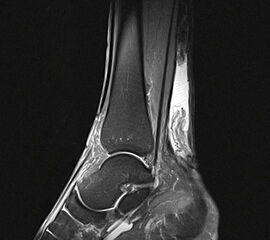

Abbildung 1

• Schwere, langstreckige degenerative Veränderungen der Achillessehne mit Ruptur (Abb. 1).